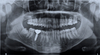

Prothèses Dentaires

Nous proposons également des prothèses dentaires pour restaurer ou remplacer les dents manquantes. Ces solutions permettent de retrouver la fonction masticatoire et l’esthétique du sourire, tout en s’intégrant parfaitement avec les dents naturelles :